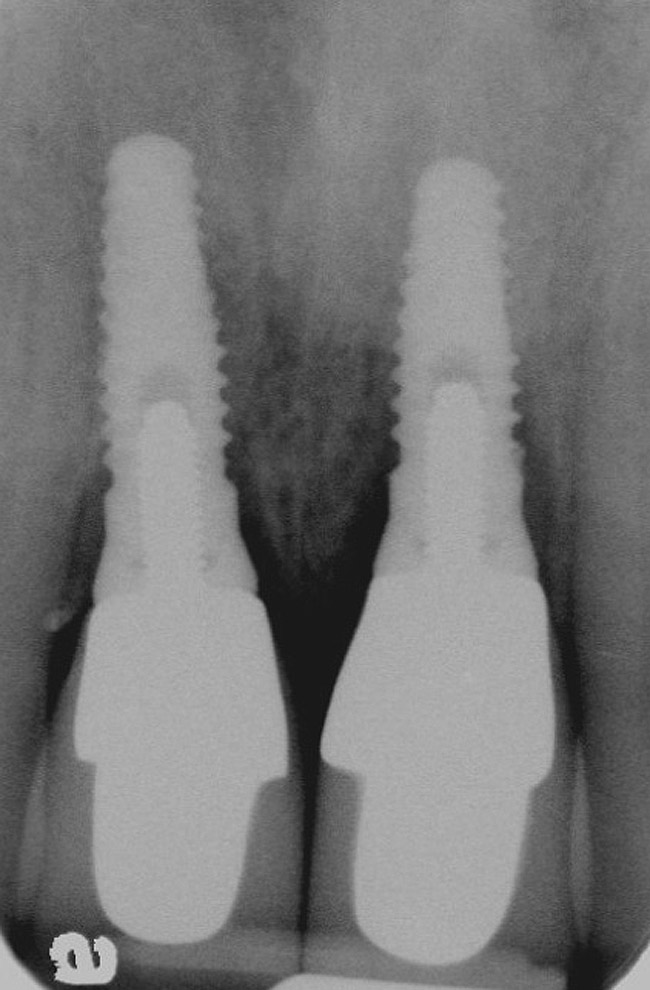

Figure 3  Periapical radiograph of implants in the Nos. 8 and 9 sites 3 years after placement. A bony peak was still present between the implants due to successful guided bone regeneration and favorable fixture spacing.

Figure 3

Figure 10   Periapical radiograph at the time of provisionalization. Note the wide peak of bone between implants Nos. 8 and 9.

Figure 10